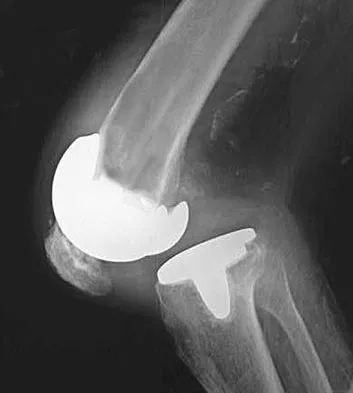

Master the AAOS & ABOS boards with practice MCQs for Set 3, covering hip and knee arthroplasty, joint reconst…

Master AAOS & ABOS boards with high-yield practice MCQs for Set 2. Covers hip and knee reconstruction, includ…